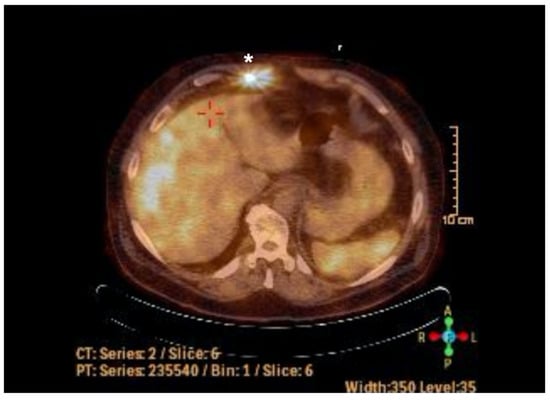

2. Case Report